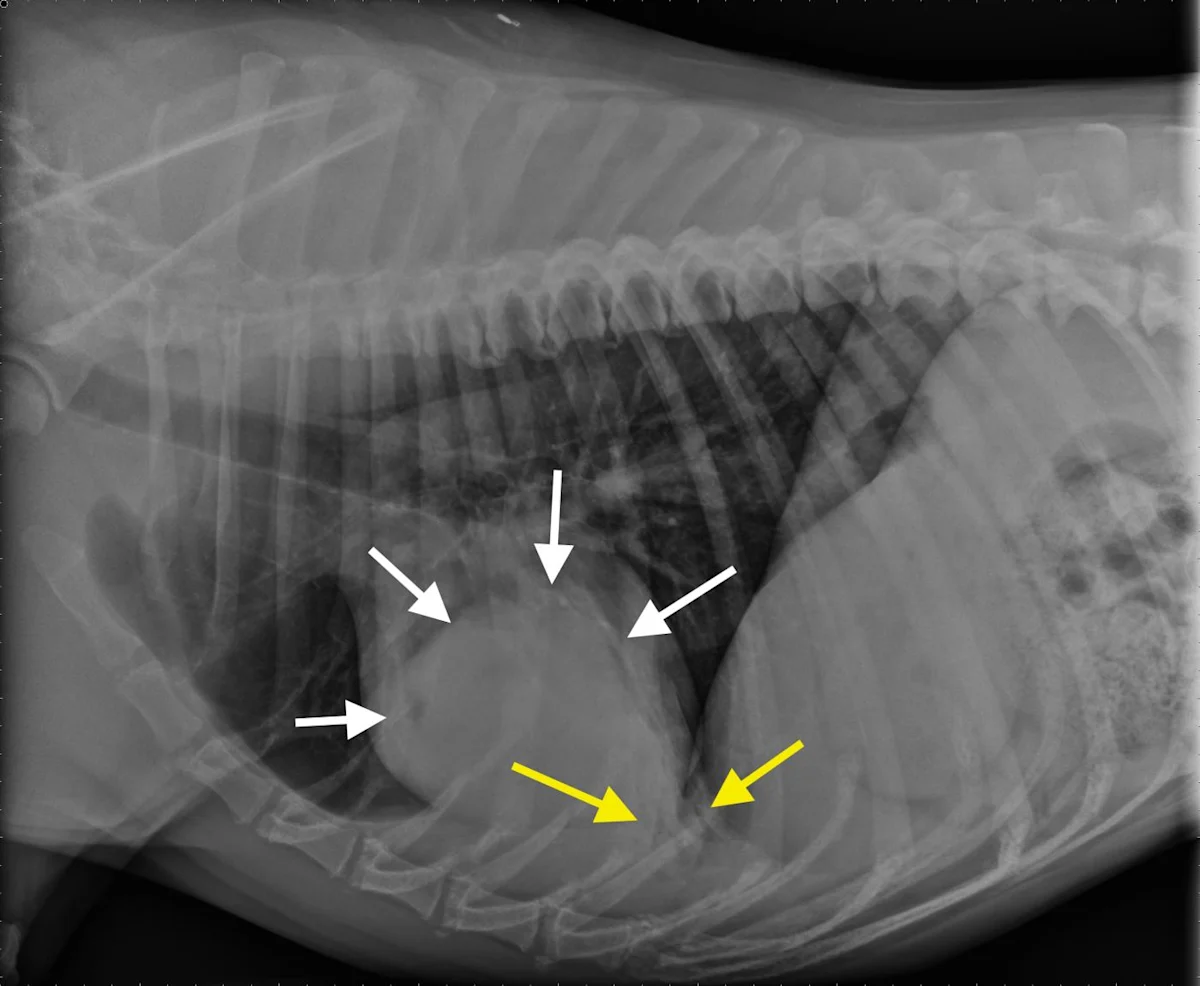

Figure 1A

Canine lung tumor

In these 3-view thoracic radiographs of an 8-year-old neutered male boxer with a lung tumor, a large soft tissue mass visibly extends to the lung lobe margins, nearly causing complete consolidation of the right middle lung lobe. Several closely spaced air bronchograms at the caudal margin of the mass are consistent with atelectasis caused by the expansile nature of the mass (Figure 1A; arrows). The apparent right mediastinal shift (ie, shifting of the cardiac silhouette to the right) in the ventrodorsal view (Figure 1C) is, at least in part, due to a moderate degree of patient rotation.

This patient underwent a right intercostal thoracotomy and lung lobectomy for tumor resection. On exposure of the thoracic cavity during surgery, it was found that the tumor was in contact with the right side of the heart, and, accordingly, occasional ventricular arrhythmias (ie, 3-4 per minute) were noted. A narrowly excised low-grade pulmonary carcinoma was confirmed via histopathology.